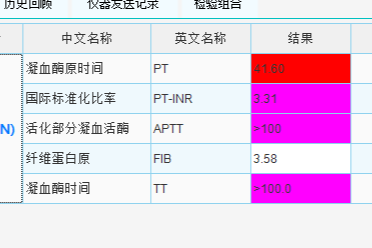

手术切除是该肿瘤的主要治疗手段。但同时因为肿瘤位于骶骨前腹膜后,位置深、骶前静脉丰富,剥离肿瘤过程中极容易出现无法控制的静脉窦出血,术中出血风险极大,手术难度极高,做这样一台手术就是打一场硬仗!

专家讨论认为,腹膜后肿瘤直径超过 10 cm,并且位于骶前,与骶前静脉丛关系密切,肿瘤右侧压迫右侧髂内动静脉,手术难度大、风险高。但肿瘤边界尚清楚,未见明显的骨质侵犯,手术关键是解剖清楚、控制好出血。

珠海市人民医院妇科团队对髂内动静脉周围的解剖熟悉、脊柱骨病科对骶前的解剖结构了解透彻、心胸血管外科对血管手术有丰富的经验、更有介入医学科必要时可以做腹主动脉的球囊,加上我们强大的体外循环装备及技术,经过多学科合作,做好充分的术前准备及术中手术预案,相信可以保证手术成功。